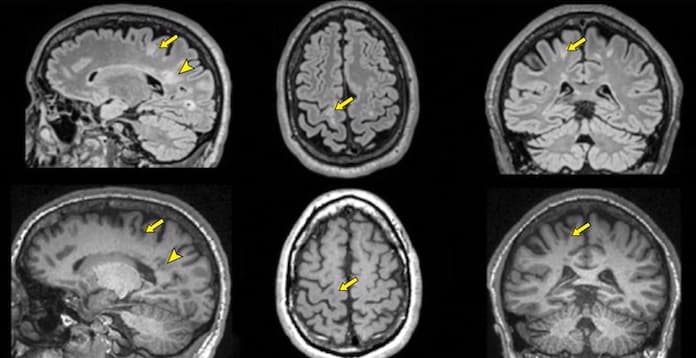

Il existe deux catégories structurellement distinctes d'agents de contraste à base de gadolinium: linéaire et macrocyclique. Dans la structure macrocyclique, le gadolinium est lié plus étroitement à l'agent chélatant et, par conséquent, moins susceptibles de libérer du gadolinium libre dans le corps. Les études précédentes étaient axée uniquement sur des agents de contraste à gadolinium linéaire. Une troisième étude, du Heidelberg University Medical Center, en Allemagne, suggère que la structure moléculaire de l'agent de contraste peut jouer un rôle dans le résidu de gadolinium. Les chercheurs allemands ont examiné rétrospectivement deux groupes de 50 patients qui avaient subi au moins six examens par IRM avec l'utilisation exclusive d'un agent de contraste à base de gadolinium linéaire ou macrocyclique. Ils ont constaté une augmentation de l'intensité du signal IRM dans des régions spécifiques du cerveau dans le groupe linéaire, mais pas dans le groupe macrocyclique.